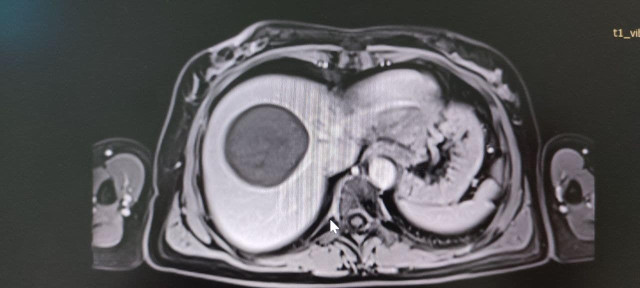

У Володимирське ТМО поступила 50-річна жінка зі скаргами на тиснення і біль у правому підребер’ї. У неї діагностували небезпечне і рідкісне захворювання – ехінококову кісту, яку хірургічно видалили.

Паразитарна кіста в печінці нагадує навколоплідний міхур, всередині якого дозрівають личинки ехінокока. Новоутворення поступово зростає і часом досягає гігантських розмірів (до 50 см у діаметрі).Ехінококозом може захворіти будь-яка людина, імунітету проти цієї хвороби немає. Хвора людина для людей, що її оточують, небезпеки не становить.